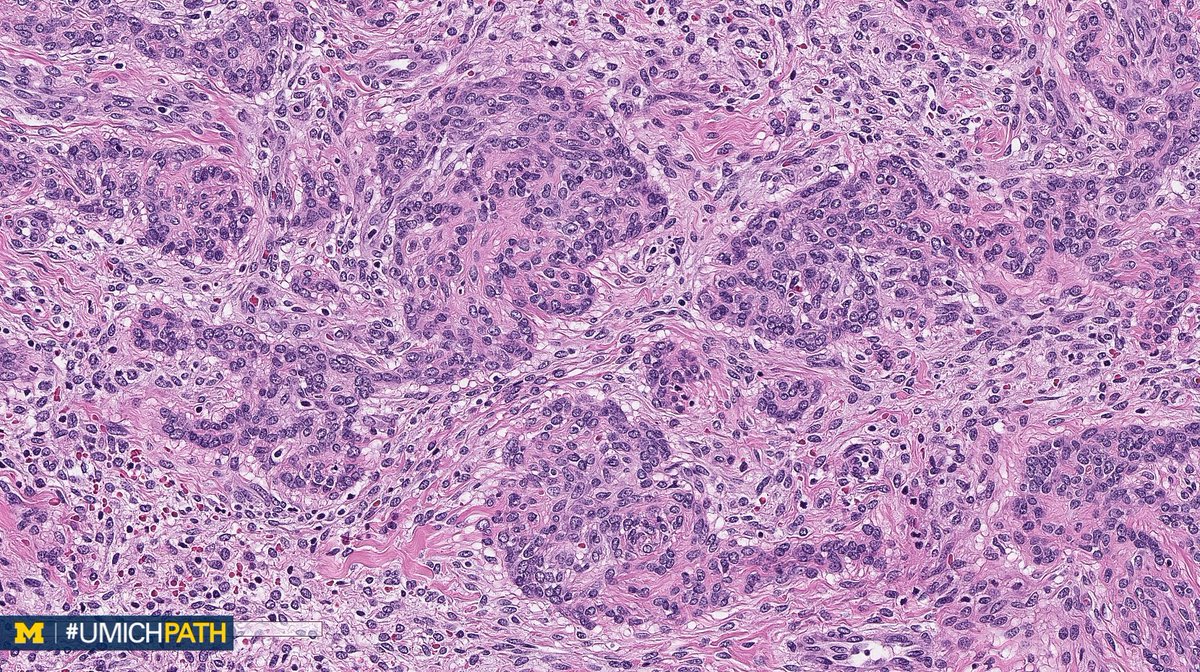

🔬#GYNPath, Day 4. ➡️What’s your #DailyDx of this uterine mass? ➡️What immunohistochemical stain would you order? ➡️We’ll tweet the answer, some quick facts, and the next case tomorrow! #UMichPath

➡️What’s your #DailyDx of this uterine mass?

➡️What immunohistochemical stain would you order?

➡️We’ll tweet the answer, some quick facts, and the next case tomorrow! #UMichPath

A: Uterine tumors resembling ovarian sex cord tumors (UTROSCT). A rare mesenchymal tumor with epithelial-like cells resembling ovarian sex cord tumors. IHC: Sex cord markers are specific, but not always positive. CD10 frequently positive. #GYNPath #DailyDx (H/T @Eggmcmullen)

UMichPath's tweet image. A: Uterine tumors resembling ovarian sex cord tumors (UTROSCT). A rare mesenchymal tumor with epithelial-like cells resembling ovarian sex cord tumors. IHC: Sex cord markers are specific, but not always positive. CD10 frequently positive. #GYNPath #DailyDx (H/T

@Eggmcmullen)